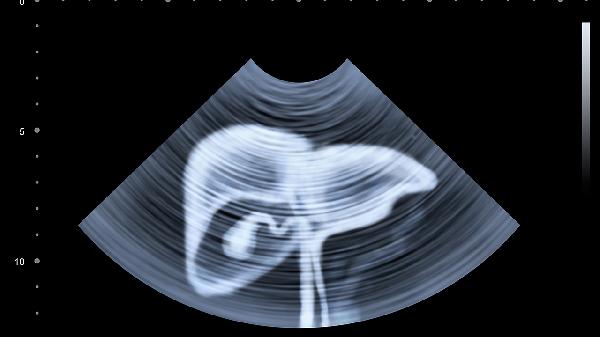

肝功能检查、肝脏B超都是常规项目。40岁以上人群建议每年检查一次,有肝病家族史的要更频繁些。